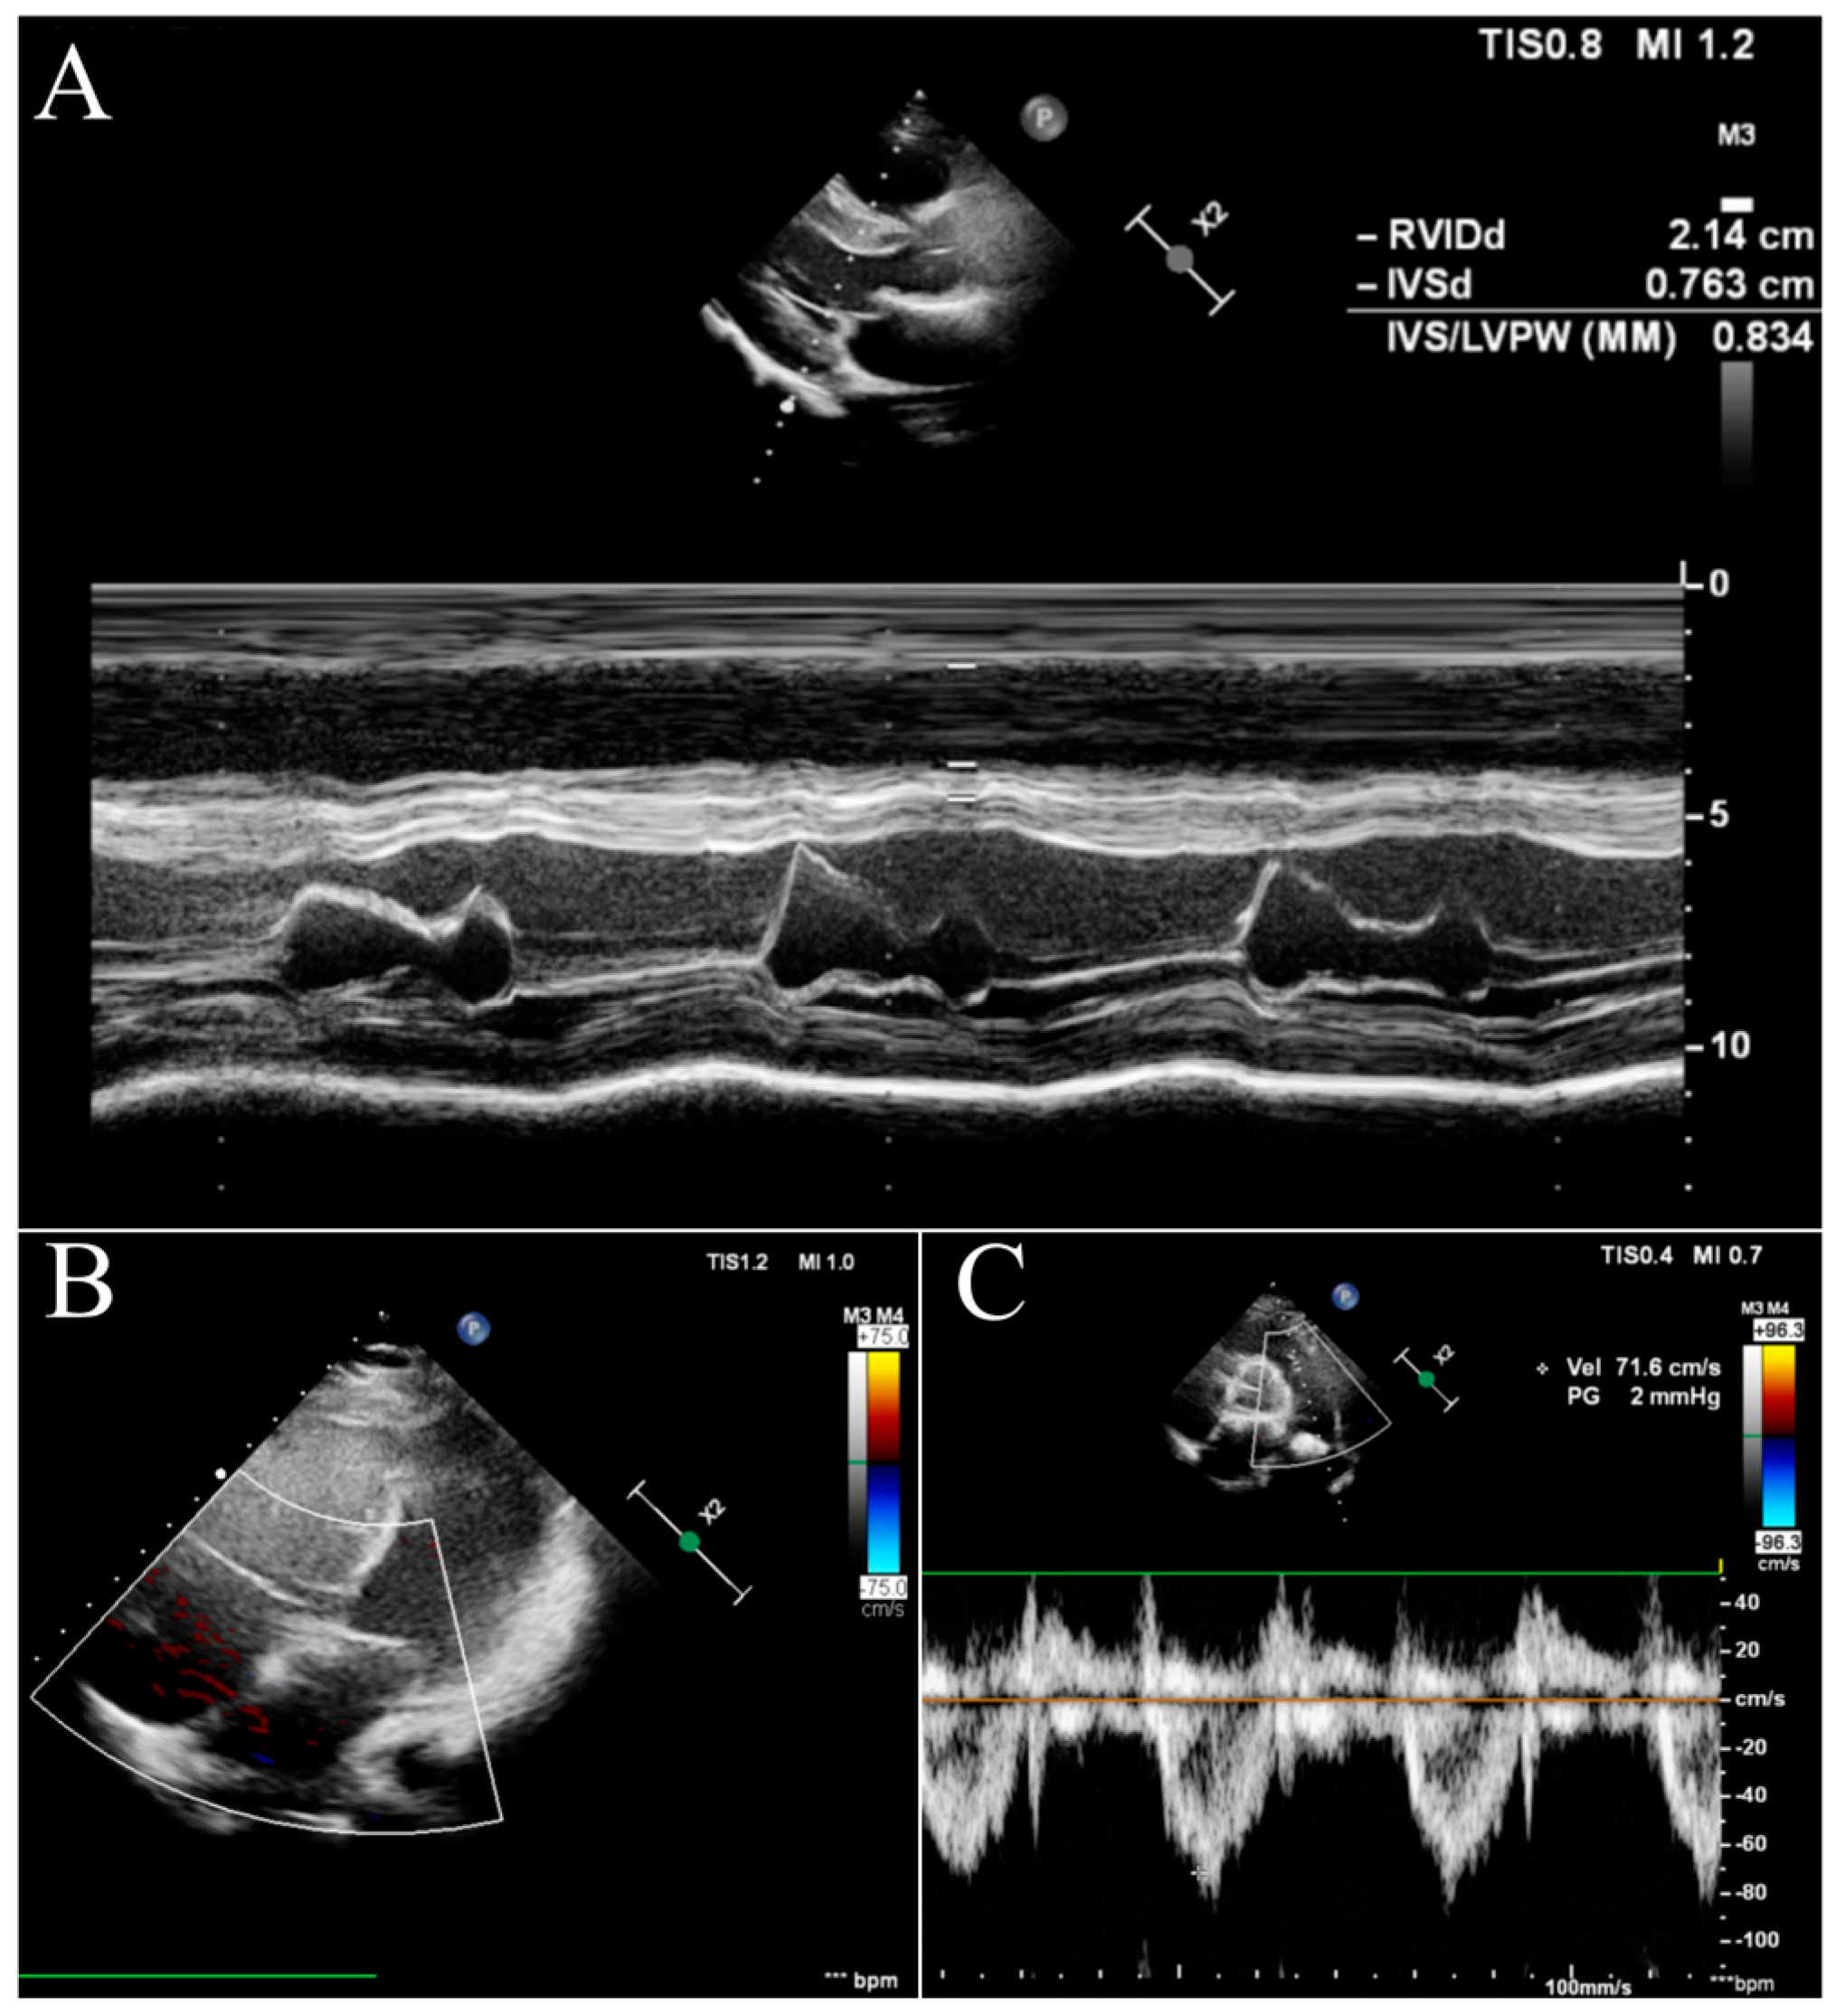

After the introduction of triple therapy, the patient underwent successful BLTx from a cytomegalovirus-positive donor in a referral transplant centre in Vienna. A cytological analysis of the postoperative material after bilateral lung transplantation finally excluded PVOD. Cardiac remodelling occurs early after BLTx as a result of a decreased RV afterload and elevated left ventricular volume preload due to the patient’s healthy lung vasculature and parenchyma of the graft [7]. The two-year follow-up was uneventful, with no signs of PH. In our patient, the echocardiography showed a progressive and rapid recovery of RV function without signs of tricuspid insufficiency (Figure 3B) and a decrease in the diameter (Figure 3A). The pulmonary artery was without valve insufficiency after transplantation, the mean flow volume (MFV) = 0.72 m/s, and we observed a complete withdrawal of PH features (Figure 3C).

Figure 3. Echocardiography in the follow-up after BLTx. (A)—parasternal long-axis view in the M-mode. (B)—apical four-chamber view with doppler at the tricuspid valve. (C)—parasternal short-axis base view with doppler at the pulmonary valve.